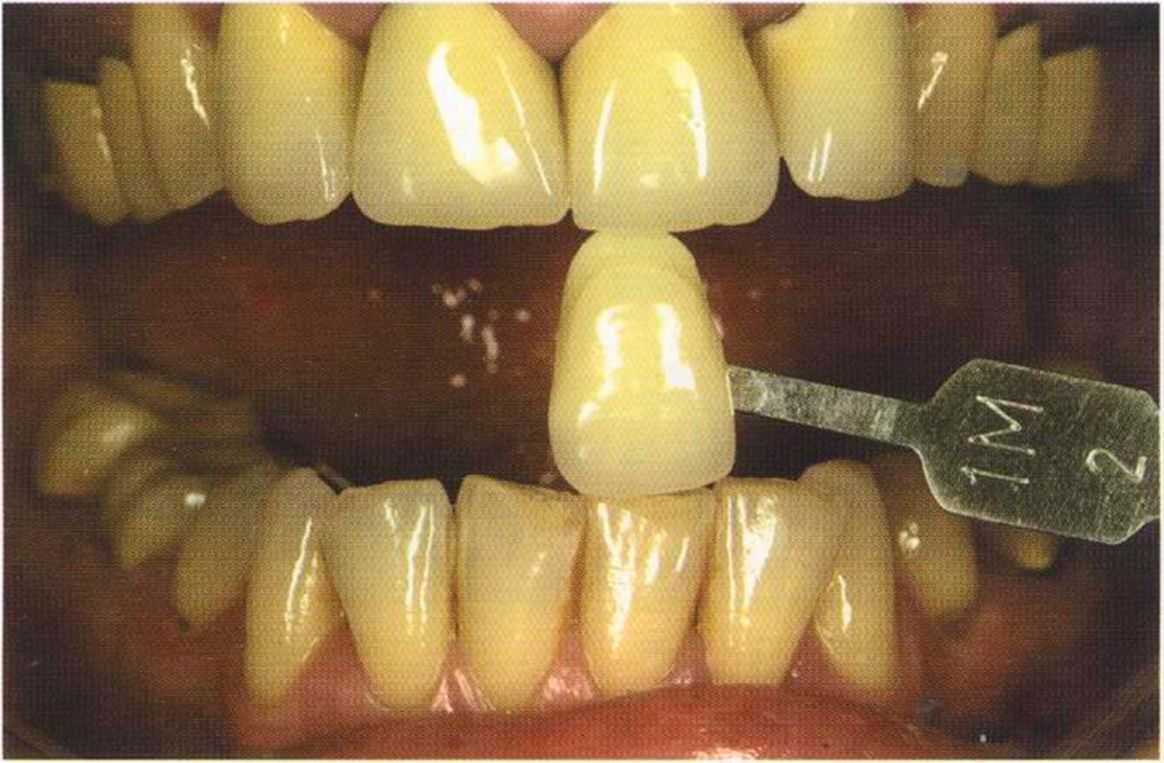

Цвет 1М1 до 1М2 основной цвет в данном случае.

Часто эти валики можно увидеть лишь под определегшым углом. Важно осмотреть работу со всех сторон. Поворот и наклон зуба затрудняют соблюдение и контроль этого

«правила отражения валиков».